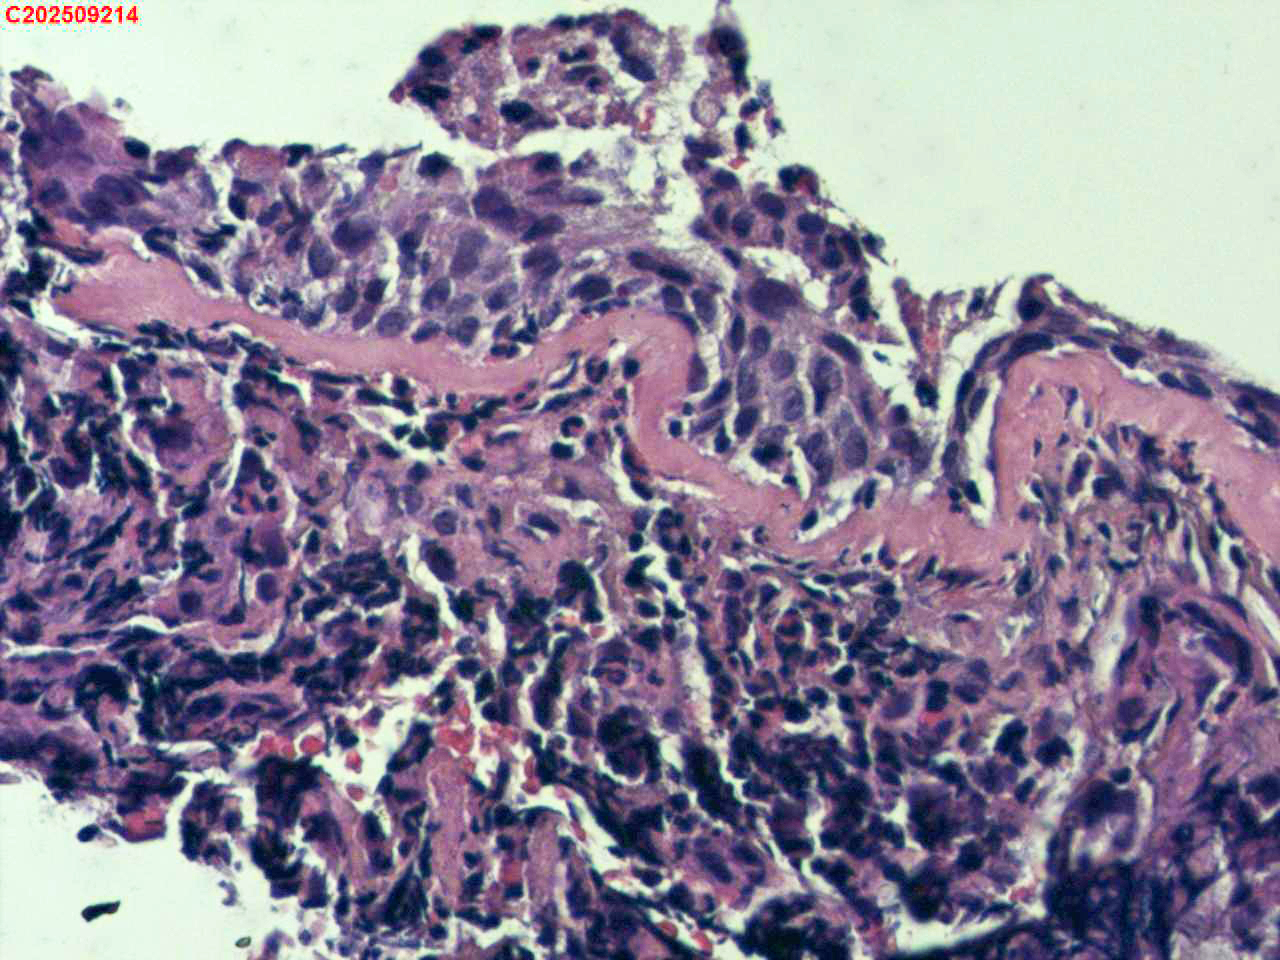

左肺下叶背段咬检组织

性别年龄59岁临床诊断肺结核?肺部感染?

标本名称左肺下叶背段咬检组织

大体所见纤支镜检查:左肺主支气管上叶、下叶及各段级支气管通畅,粘膜无充血,背段外亚段远端可见疑似白色痰栓,灌洗支气管刷检并镜下尝试活检钳清理,发现其质硬考虑为新生物并咬检,该部位深远,且咳嗽及呼吸干扰取材不理想。

毛霉菌病